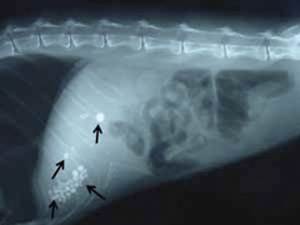

Для иследования печени, поджелудочной железы и желчного пузыря также могут быть использованы рентген брюшной полости и УЗИ. В некоторых случаях, когда лабораторные анализы и другие методы не помогают при диагностике, может потребоваться диагностическая операция – лапаратомия. Диагностическая лапаратомия также имеет преимущество одновременного исправления проблемы, если она будет найдена в процессе исследования.